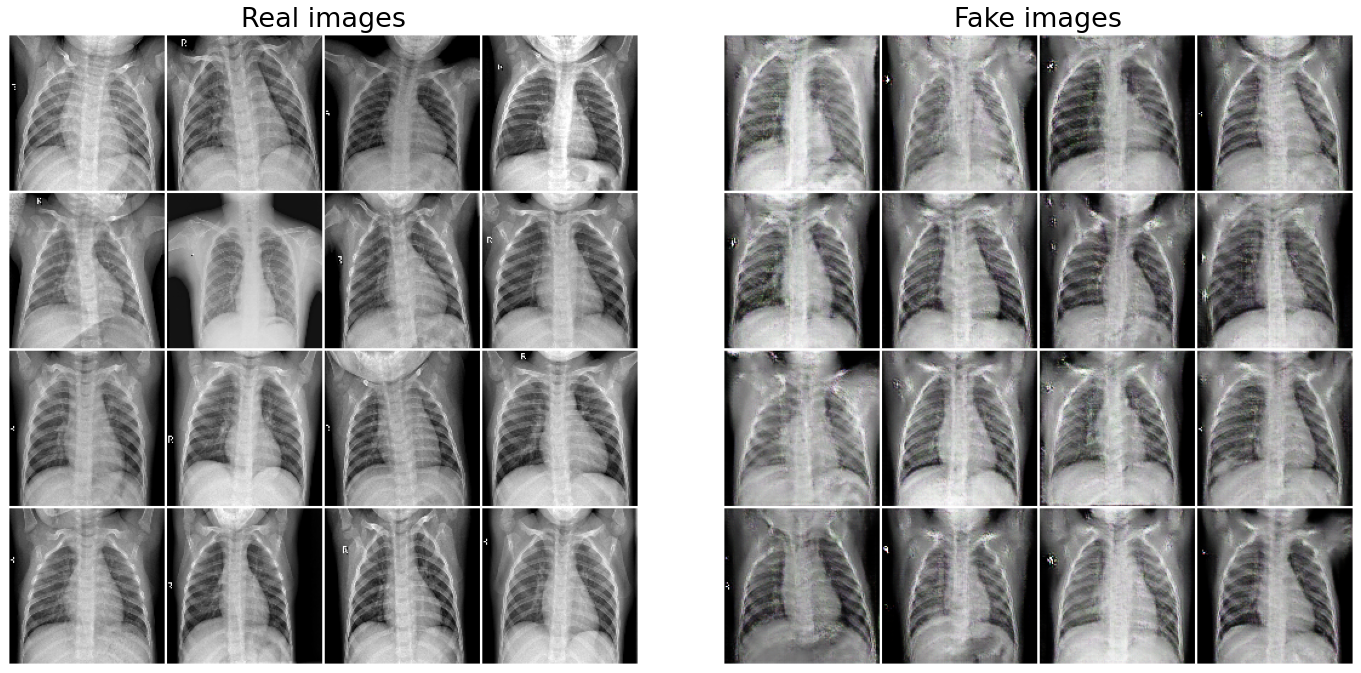

The DCGAN was trained for 500 epochs and in just around 50 epochs, the DCGAN was able to generate images that resembled the chest X-ray images and then the quality of generated images further improved over 500 epochs.

Figure 3: Images from Original dataset (Real) and Images generated by the generator of DCGAN (fake)

For comparison, we show a grid of Real images (original data) and the fake images (generated images) in the Figure 3.